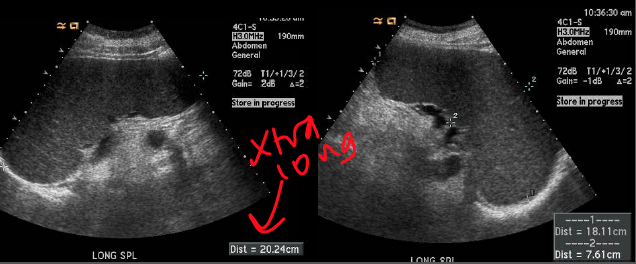

what are the dimensions of this spleen?

is this normal?

long 10.25cm

AP 4.22 cm

a bit small perhaps

which plane are each of these spleens in? how can you tell?

lt long, rt trans

look for the hilum.

What is it called when the spleen is larger than normal?

splenemegaly